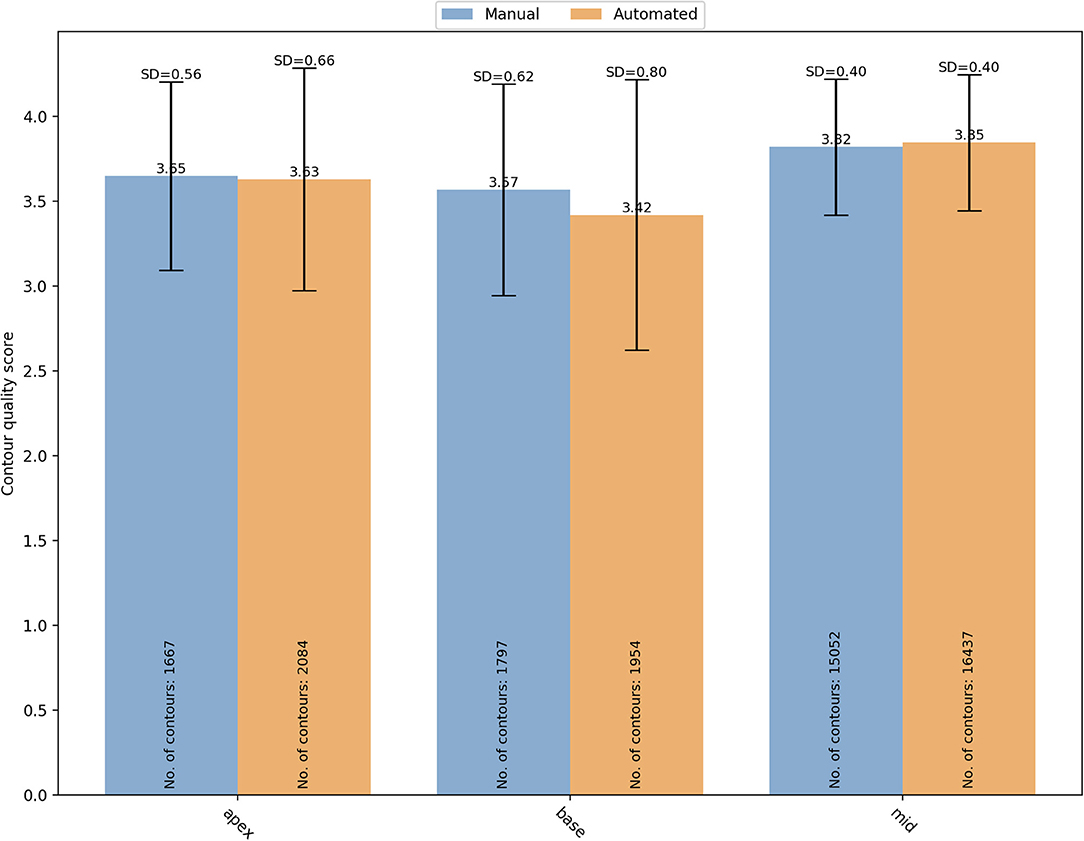

The segmentation complexity depends also on the slice level of the image. For instance, basal and apical images might be more challenging to contour than the mid ventricular images. For that reason, the contours quality scores were also analyzed based on the SAX slice level (Figure 6). For manual segmentation, the mean quality scores were 3.65 ± 0.56 (n = 1,667), 3.57 ± 0.62 (n = 1,797), and 3.82 ± 0.40 (n = 15,052), for apical, basal, and mid-ventricular levels, respectively. Compared to mid level, both basal (OR (95% CI) = 0.18 (0.13–0.25) and apical (OR (95% CI) = 0.44 (0.31–0.63) had significantly lower quality scores (p < 0.0001). Whereas the quality scores for the automated contours were 3.63 ± 0.66 (n = 2,084), 3.42 ± 0.80 (n = 1,954), and 3.85 ± 0.40 (n = 16,437), for apical, basal, and mid-ventricular levels, respectively. Compared to mid level, both basal (OR (95% CI) = 0.06 (0.04–0.09) and apical (OR (95% CI) = 0.29 (0.19–0.44) had significantly lower quality scores (p < 0.0001). A significant interaction was found (p < 0.0001) suggesting that reductions in quality for basal levels were more pronounced for the automated scores. Instead, the interaction was not significant for the apical levels (p = 0.17).

Figure 6. Distribution of the overall mean quality scores for different SAX slice levels (apical, basal and mid) with manual (blue) and automated (orange) segmentation. SD, standard deviation.